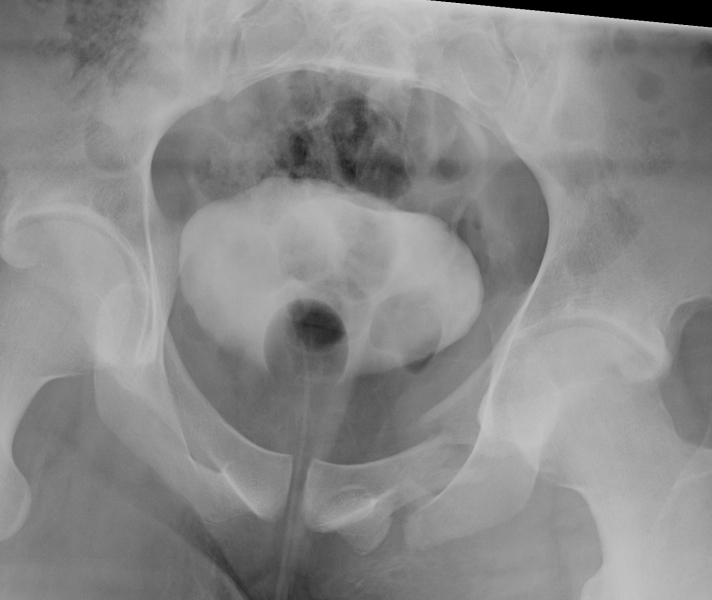

CT

Configuration

1-2 mm sections

CT reconstruction

- remove head to view acetabulum

- beware volume averaging

- used to guide surgery

Diagnose

Loose bodies

Femoral head fractures

Subtle subluxation

Articular steps

Roof arc measurement

B. CT subchondral arc

- 10 mm below subchondral bone of roof

- similar to xray roof arc measurements

3. Stability / Concentric reduction

Subluxation

- incongruency between the head and the roof

- poor clinical results are obtained in more than 50% of fractures in which the head is subluxed

- may also have an element of dynamic instability, with certain posterior wall fractures

Any subluxation on CT demonstrates clinical instability

- fractures affecting 40% or more of the posterior wall are usually associated with instability

- fractures less than 40% should be screened for stability under II